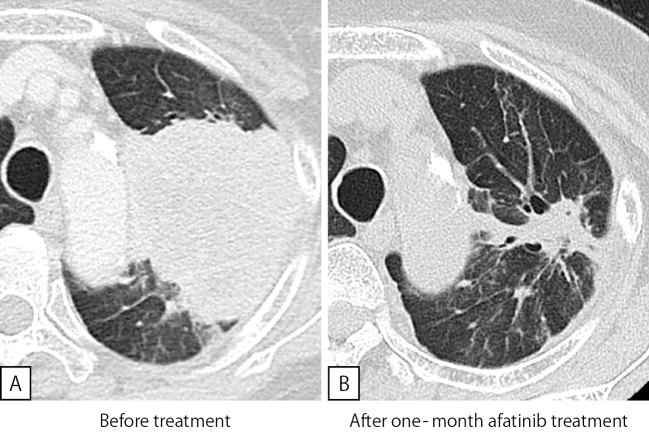

The Afatinib Response to EGFR E709G-mutated Lung Cancer.